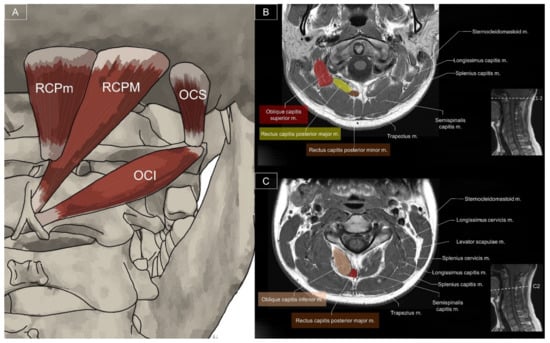

6.1. Sub-Occipital Muscles

6.1.1. Anatomy

6.1.2. Sonographic Scanning

6.1.3. Clinical Relevance